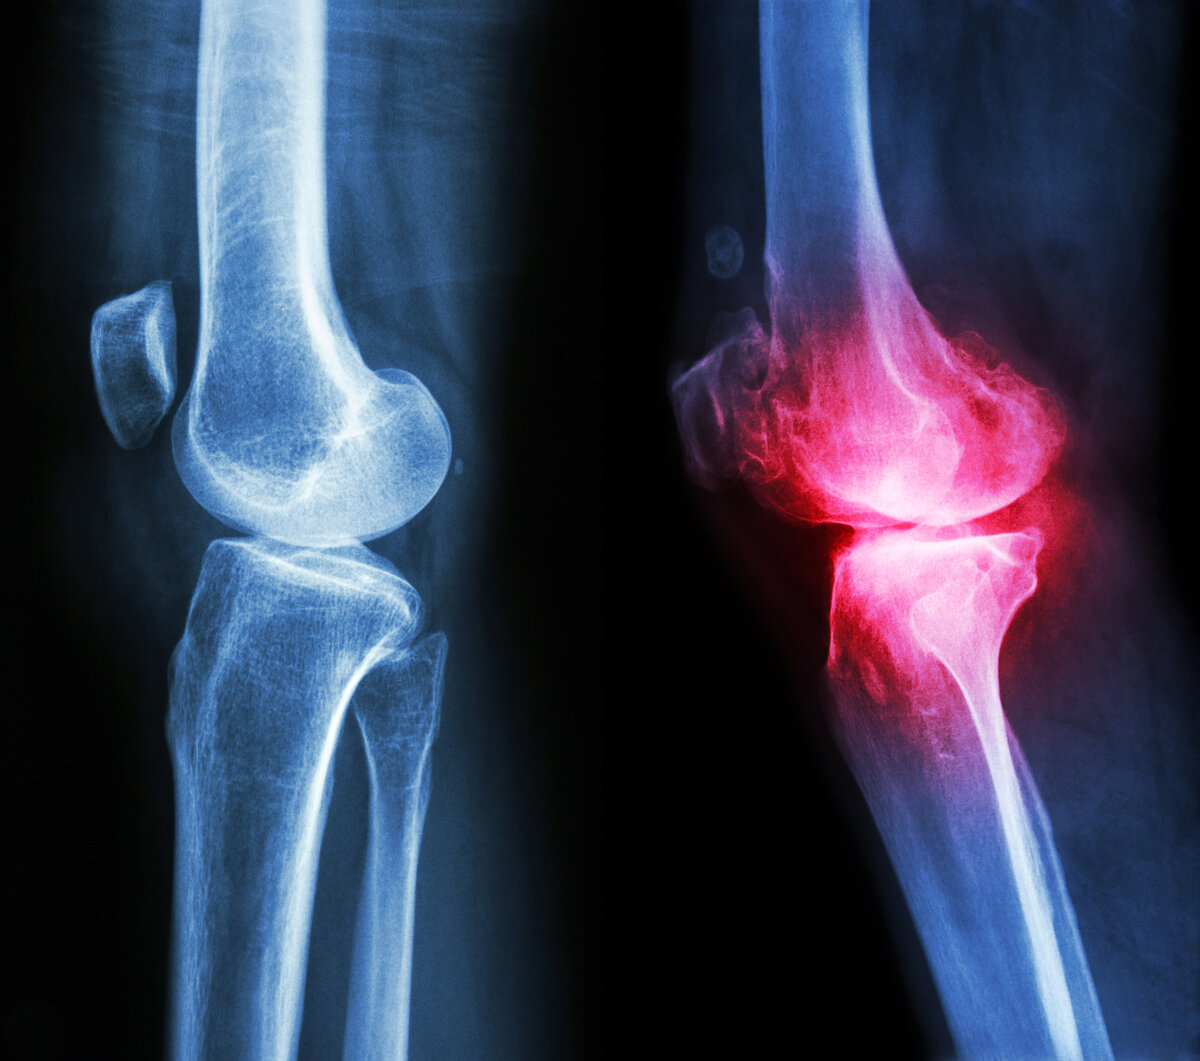

Одной из самых часто встречаемых разновидностей артроза является гонартроз. Гонартроз – это артроз коленного сустава. При этом заболевании истончается и разрушается хрящевая ткань, а затем формируются обширные костные разрастания в коленном суставе. При запущенной стадии болезни снижается способность к самостоятельному передвижению.

МАТЕРИАЛ ПОДГОТОВЛЕН В РАМКАХ ОБРАЗОВАТЕЛЬНОГО ПРОЕКТА АППТЕКА25.РФ ВРАЧОМ ТРАВМАТОЛОГОМ-ОРТОПЕДОМ ВЫСШЕЙ КВАЛИФИКАЦИОННОЙ КАТЕГОРИИ ВАХРУШЕВЫМ НИКОЛАЕМ АЛЕКСАНДРОВИЧЕМ. Артроз – это заболевание хронического типа, при котором из-за нарушения обменных процессов прогрессируют дегенеративно-дистрофические изменения в суставных структурах с постепенным разрушением хрящевой ткани. Артроз – одно из самых распространённых заболеваний. Сейчас в России из-за него страдает примерно 7% населения. Сегодня подробнее расскажем, какие существуют современные методы лечения артроза и последствий травм. 1. Лечение гонартроза Одной из самых часто встречаемых разновидностей артроза является гонартроз. Гонартроз – это артроз коленного сустава. При этом заболевании истончается и разрушается хрящевая ткань, а затем формируются обширные костные разрастания в коленном суставе. При запущенной стадии болезни снижается способность к самостоятельному передвижению. Симптомы гонартроза: Лечение гонартроза непростое